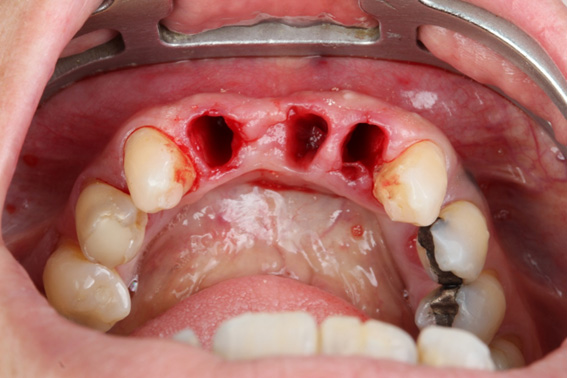

3 | Alveoli immediately after tooth extraction. Occlusal view